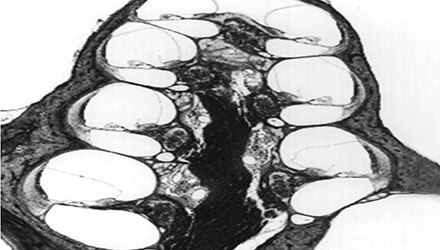

3、膜迷路破滅

膜迷路積水致膜迷路脹破,內外淋巴液混合,刺激神經感覺細胞導致眩暈、耳鳴、耳聾,裂口愈合則病變暫時恢復。下圖左為前庭膜膨大,右圖為前庭膜破裂,內外淋巴交混。